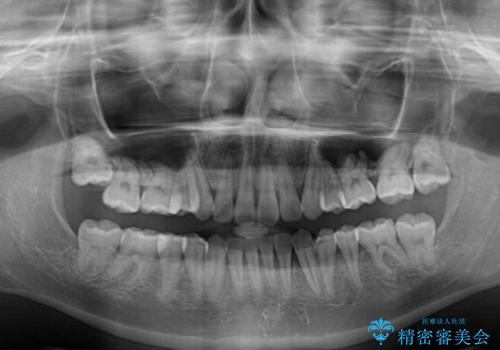

- 上顎前歯のデコボコを気にして来院された患者様です。

口元の突出感はなく、上顎のみに顕著な叢生が認められました。

上顎の左右第一小臼歯2本を抜歯し、ワイヤー装置にて歯列を整えることとしました。

奥歯の咬み合わせがなかなか定まらず、スペースが閉じるまでに時間がかかりましたが、最終的には正中を合わせることもできました。